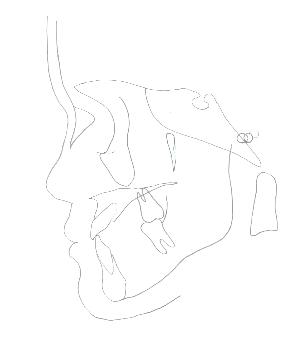

治療前模型       治療後予測模型

診査の結果をもとに、現状と治療計画・治療費などについて説明します。矯正でもっとも大切なのが診断です。骨格、歯の大きさなどすべてを審査してもっとも適切な治療を選択します。